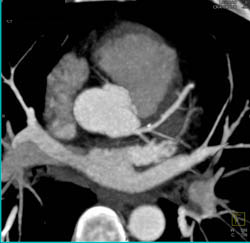

Calcified Plaque in All Vessels